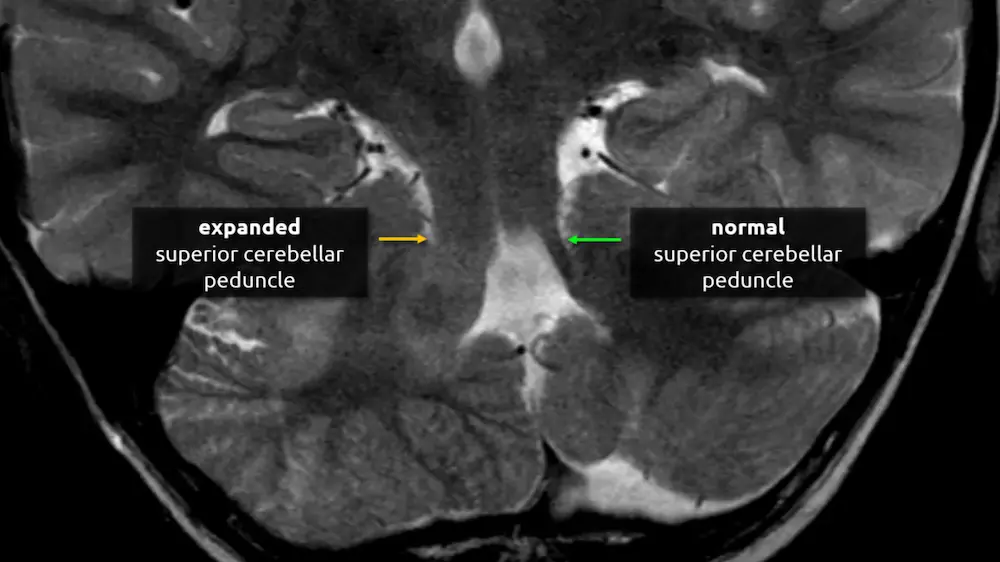

2. Superior cerebellar peduncles

The superior cerebellar peduncles are the most superior of the three paired white matter bundles that connect the cerebellum to the brainstem. Their fibers are mostly efferent, beginning at the dentate and emboliform nuclei of the cerebellum and terminating at the contralateral thalamus and the red nucleus, located in the upper midbrain (see level 3).

Atrophy of the superior cerebellar peduncles can be seen in several conditions, such as progressive supranuclear palsy and other Parkinsonian disorders.

a. What brainstem structure is asymmetrically enlarged?